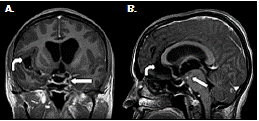

Por último, se recibió un resultado positivo de la prueba de Western blot para cisticerco en suero y en líquido cefalorraquídeo. El análisis retrospectivo de la resonancia magnética cerebral permitió concluir que se trataba de una neurocisticercosis racemosa (sic) (figura 1) y (figura 2) con vasculitis secundaria a la intensa reacción inflamatoria, probablemente generada por la muerte del parásito.

Según los hallazgos en las imágenes de resonancia magnética cerebral, los casos informados se clasificaron como neurocisticercosis extraparenquimatosa con quistes racimosos en el espacio subaracnoideo asociados a la intensa reacción inflamatoria (figura 1), (figura 4).

En los dos casos que se presentan, la neurocisticercosis racemosa (sic) se acompañó de hidrocefalia y aracnoiditis; en el primer caso, además, se detectó vasculitis de la arteria cerebral media derecha en sus porciones proximales adyacentes a las cisternas de la base y la silviana derecha, relacionada con la presencia de cisticercos (figura 1). En el segundo caso, se detectó dilatación y obstrucción del cuarto ventrículo por aracnoiditis (figura 3), hallazgo que explica la causa del vómito incoercible, debido a su estrecha relación anatómica con el área postrema (control del vómito).